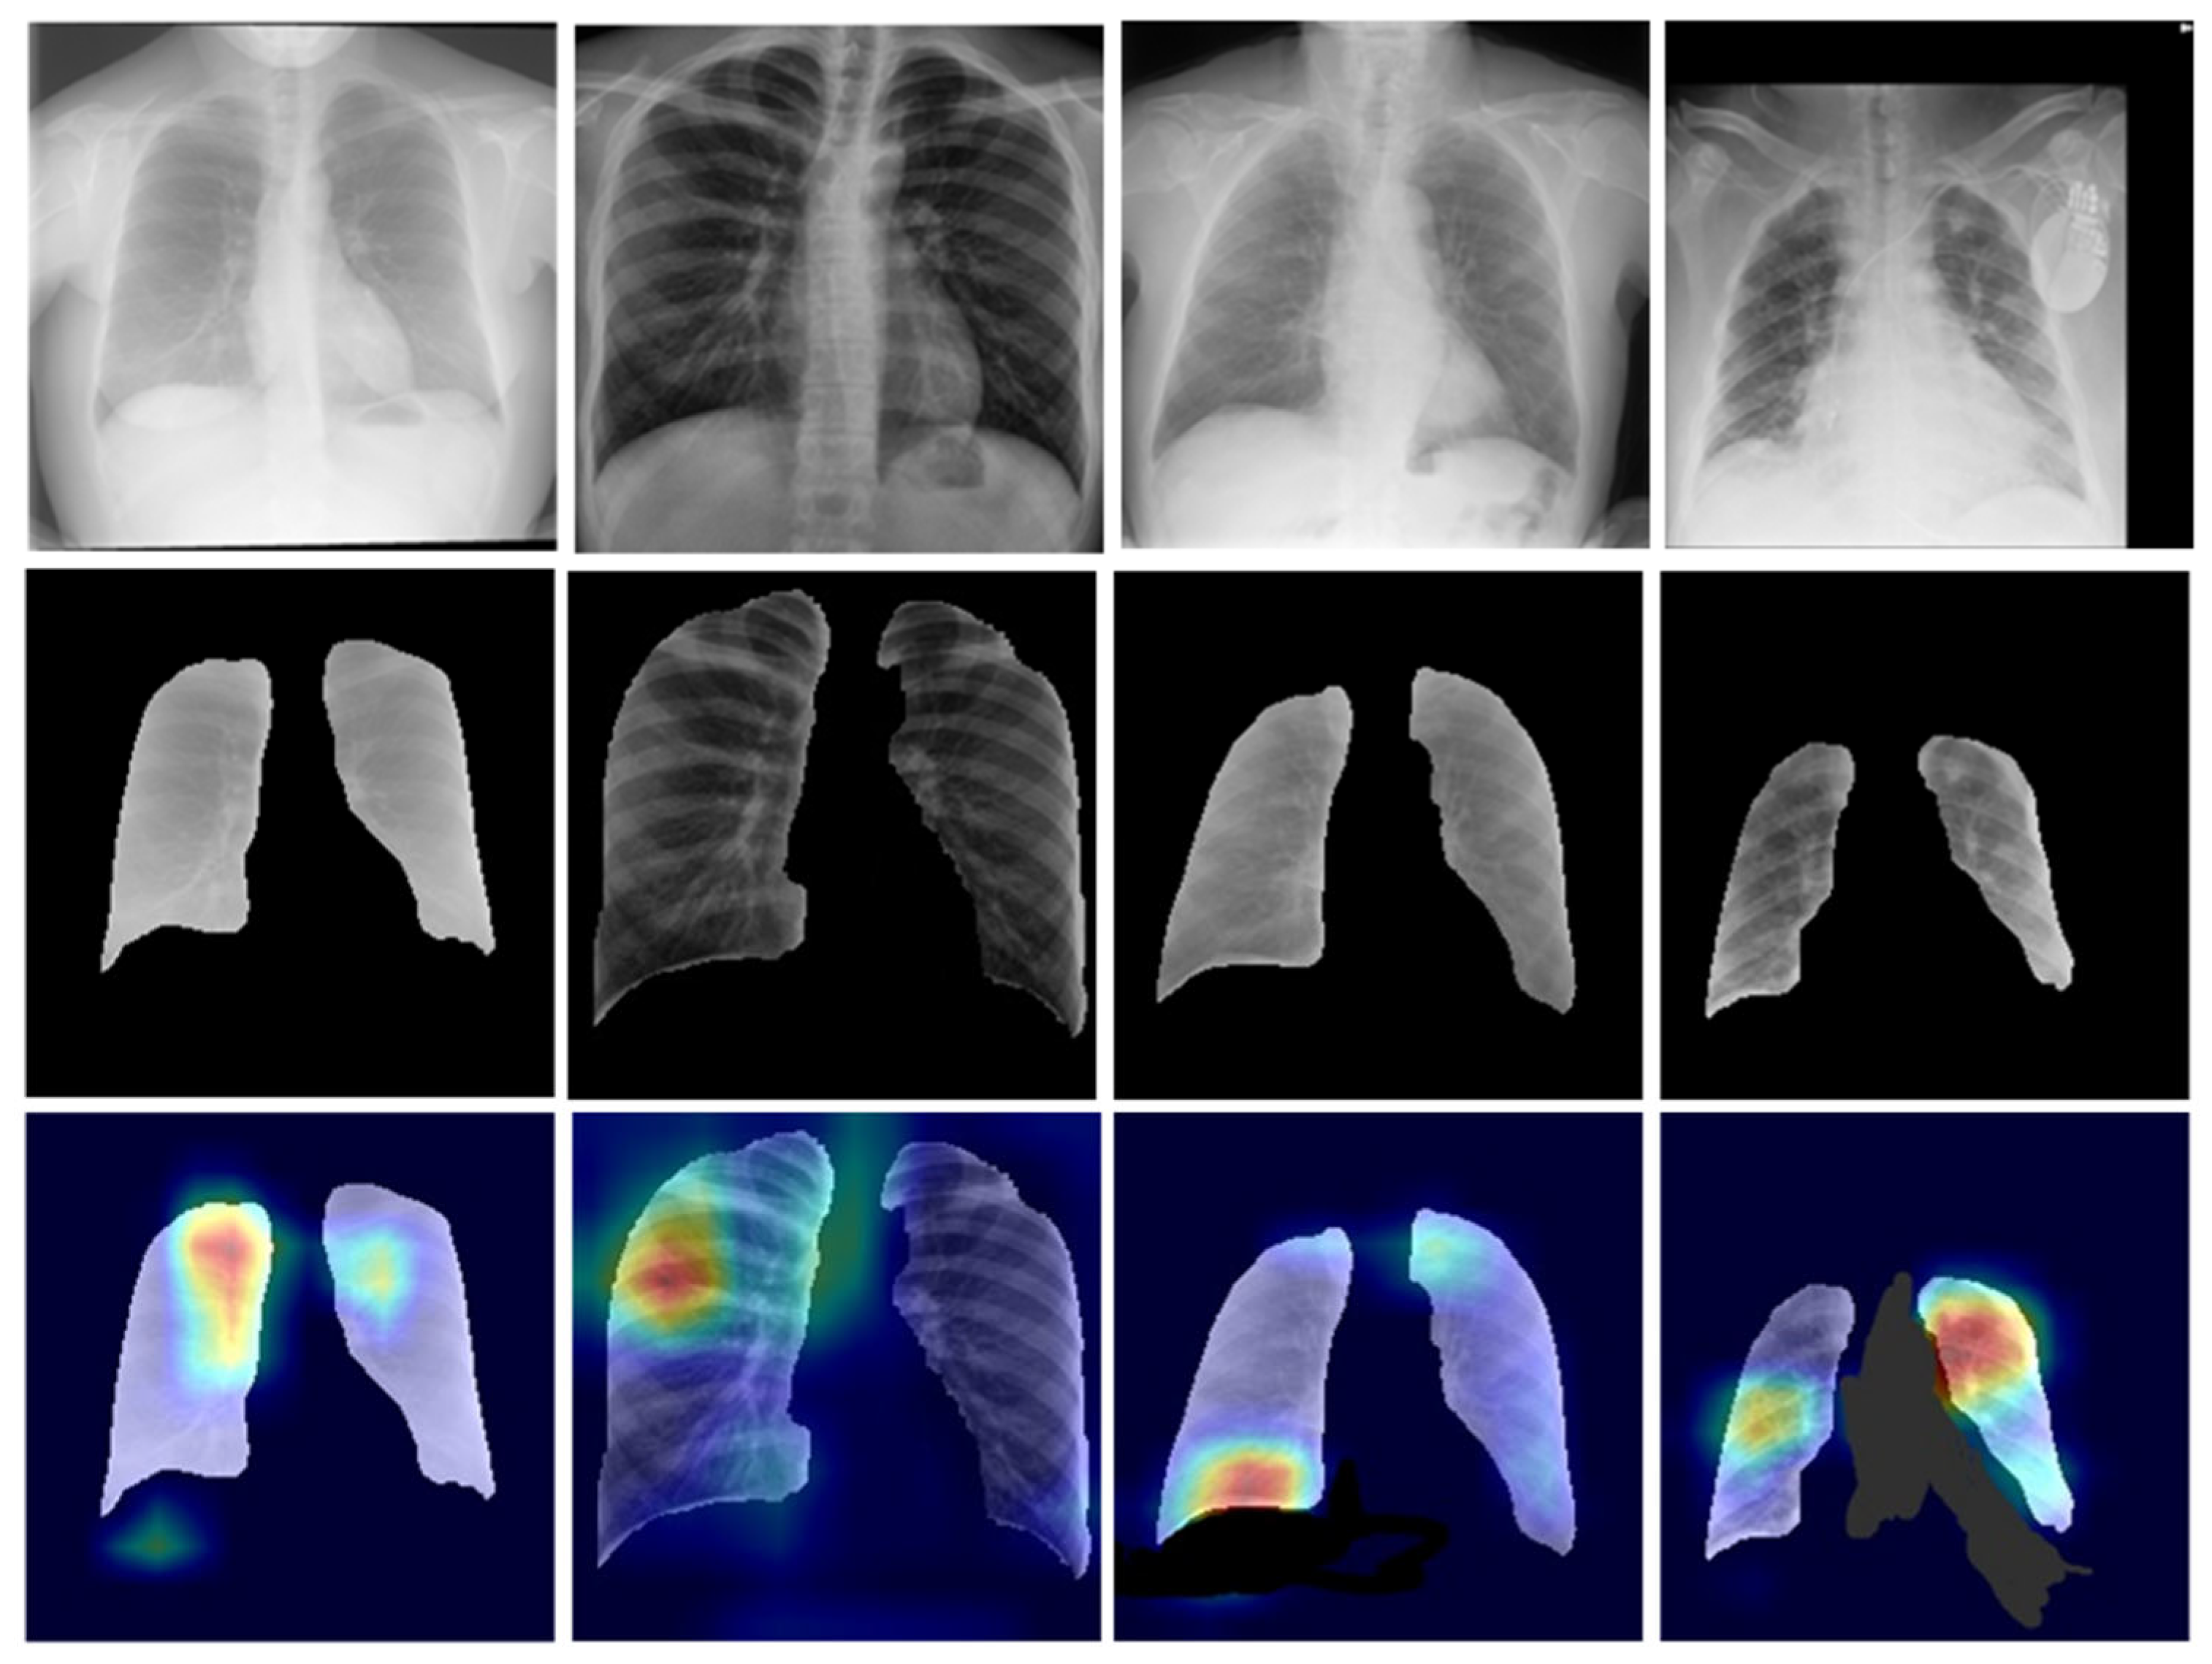

3.1.6. Segmentation of the Classification Dataset

3.2.3. Heatmap Visualization: An Explainable AI Model